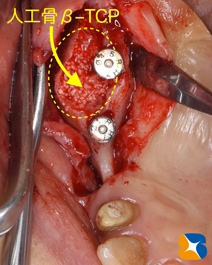

インプラント移植と骨の増殖を同時に行いました。

骨の増殖には、人工骨β-TCPとCGF(フィブリノーゲン)を混ぜた物を使用しています。

人工骨の変形や流出を避けるために、CGFメンブレンを利用しました。

これは、採血した自己血液を利用して、院内で製造したものです。

当院は、近畿厚生局が認可した再生医療加工施設です。